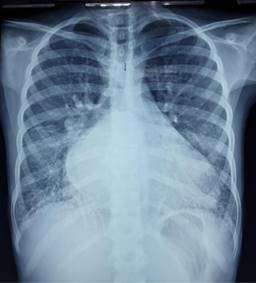

One of the first-degree relatives of the patient had genetic investigations which reported a heterozygous mutation in gene TNNI3, classified as a variant of uncertain significance associated with Dilated cardiomyopathy 2A (OMIM:611880), Dilated cardiomyopathy 1FF (OMIM: 613286), Restrictive cardiomyopathy familial 1 (OMIM: 115210), Hypertrophic cardiomyopathy 7 (OMIM: 613690), all of which have an autosomal dominant inheritance pattern. A diagnosis of cardiomyopathy was suspected due to the clinical presentation and family history. Findings in the initial chest X-ray (Figure 1) revealed cardiomegaly, bilateral atrial enlargement, and pulmonary congestion, and those on the ECG (Figure 2) showed a sinus rhythm, bilateral atrial enlargement, and right ventricle strain supported the suspected diagnosis. The echocardiogram (Figure 3) confirmed the bilateral atrial dilation (LA; 34.8 cm2, RA: 34.1 cm2), an E/A ratio greater than 2, and a PSAP of 47 mmHg, and a left atrial volume of 154 cm3. Using the recommendations for chamber quantification by the European Society of Cardiology, those values were classified as severely abnormal as the atrial volume was above 73 mL. Therefore, indicating severe damage to the left atrium. Abdominal ultrasound confirmed hepatomegaly with dilation of suprahepatic veins. PCR SARS-CoV-2 was negative.

Figure 1: Image corresponding to chest X-ray on arrival. Cardiomegaly with notable biatrial hypertrophy and pulmonary venous congestion.